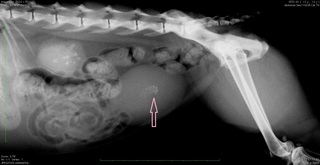

脾臓摘出手術、無事終わりました☆

お熱があって、息が荒いというワンちゃん ひどい貧血でした 超音波検査で、脾臓と肝臓にしこりがあり、 お腹の中で、出血を起こしていることがわかりました とにかく、まず輸血をしなくちゃ!! ということで、おうちのワンちゃんに ドナー協力して頂き、...